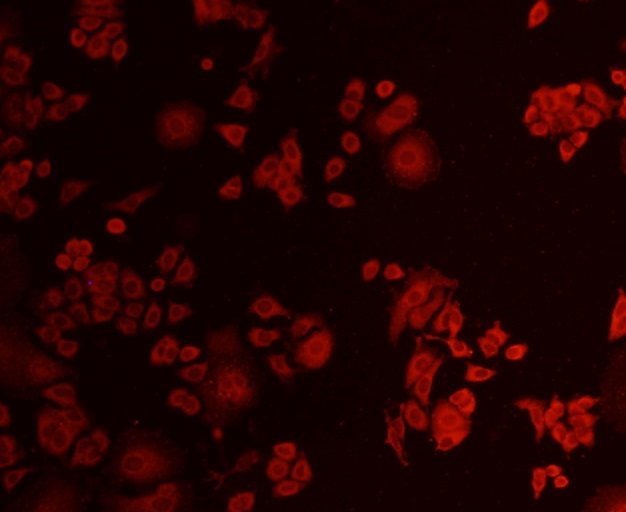

ApplicationsFlow Cytometry, Western Blot, ImmunoCytoChemistry, ImmunoHistoChemistry

- Antibody SpecificityThis antibody detects endogenous levels of AKT1 and does not cross-react with related proteins.

- ApplicationsFlow Cytometry, Western Blot, ImmunoCytoChemistry, ImmunoHistoChemistry

- Scientific DescriptionMouse monoclonal antibody to AKT1

![IHC-P analysis of human prostate carcinoma section using GTX02583 AKT1 antibody [rAKT1/2491].](https://www.genetex.com/upload/website/prouct_img/normal/GTX02583/GTX02583_20210319_IHC-P_1_w_23053122_113.webp)